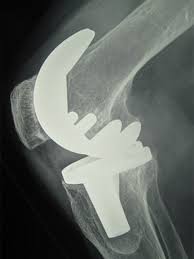

The company ORTHOPEDIC NIKIFOROV was founded in 1998 by the candidate of medical sciences. doctor of orthopedic-traumatologist of the highest category Nikiforov IA Owing to high professionalism and results of work, ORTONIC has gained well-deserved reputation and reputation among colleagues and population of Dnepropetrovsk region and CIS countries (Russia, Moldova, Armenia, etc.). The principle of the enterprise is NO IMPOSSIBLE, it is based on knowledge, experience and active implementation of modern technologies in orthopedics and traumatology. Conservative methods of treatment include individual selection of medicines, therapeutic blockades, manual therapy, massage, physiotherapy (vibration table, magnetotherapy, bioptron, electromyostimulation, etc.), rehabilitation with the suggestion of the necessary concomitant devices and means for the fastest recovery (corsets, bandages, various joint fixators, crutches, walking sticks, etc.). Various minor invasive interventions (chymonucleolysis, vertebroplasty, kyphoplasty, percutaneous nucleoplasty using cold plasma) that are performed on an outpatient basis are successfully used to treat problems associated with spine pathology. The latest modern treatment methods introduced in our company are endoscopic operations using the TYSSES technique of Joimax (Germany) with intervertebral hernias, stenosis and other pathologies of the spine, which allow to avoid complications occurring during open operations and the accompanying general anesthesia. We have many years of successful experience in traditional and modern minimally invasive endoprosthetics of large and small joints, which remains the main direction of our activity. Our company is the exclusive representative of the German company IO International Orthopaedics Holding GmbH, which based on the already known prostheses, its ideas and technological capabilities, has developed and implemented a new concept in hip replacement - an artificial joint prosthesis (ICON). We assist interested colleagues in training the operative technique for installing an artificial joint prosthesis - ICON, both in the workplace and in Germany. For 20 years we have been successfully cooperating with Sanitatshaus Gerd Klinz ortho team, an enterprise that for 20 years has been one of the leading places in Germany for the production of functional prostheses of the upper and lower limbs, as well as cosmetic prostheses of limbs and other body parts (nose, ears, eyeballs, fingers). We have an atmosphere of friendliness and human participation. Politeness, benevolence, the desire to understand and help is the basis of our attitude towards patients. We are always glad to see you and will do our best to make you feel great! We are waiting for you at: Ukraine, Dnepr, Gagarin Ave., 13 (under reconstruction) on all questions to address: tel .: +38 (050) 488-88-92 E-mail: orthonik.ukr@gmail.com Germany, Spine Nano Klinik, Zeppelinstr. 21, Potsdam Tel. +4901801121919 E-mail: kmw.nikiforov@hotmail.de